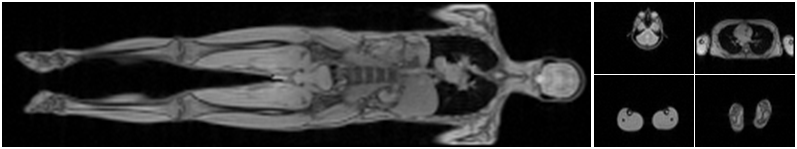

The radio frequency power in magnetic resonance imaging leads to tissue heating and has to be monitored by measuring the specific absorption rate, which depends on the position of the patient in the scanner. For current high-resolution scanners, this imposes restrictions because either fewer slices can be acquired or the in-plane resolution has to be reduced. Manifold learning can be used to estimate the position of the patient in the scanner [22].

First, low-resolution images are acquired while the bed that the patient lies on moves inside the scanner. The images are embedded in a low-dimensional space, where each axial image is associated with a body part (head, neck, lung, etc.) using a nearest-neighbor classifier. By knowing which slices correspond to which body parts, we can estimate the position of the patient in the scanner. It is important that the estimation be done in real-time to provide the position information before the high-resolution scan starts. In this application, we can apply manifold learning offline on a large database of scans. Then during the actual scan, we use an out-of-sample extension to project the acquired slices into the low-dimensional space. For large training datasets, it may be difficult to meet the time requirements with kernel ridge regression. Consequently, the reduction to a small set of support vectors offers a substantial advantage.

We run experiments on 13 whole body scans, such as the example shown in Fig. 3. A medical expert assigned an anatomical label (head, neck, lung, abdomen, upper leg, and lower leg) to each of the axial slices (6464 pixels). We apply Laplacian eigenmaps to embed the high dimensional slices in a two-dimensional space; we use a 40-nearest-neighbor graph with a heat kernel of temperature . To predict the anatomical label of an axial image, we perform nearest-neighbor classification in the learned low-dimensional space. We repeat this classification procedure for different values of error tolerance ranging from to .

We compare the classification performance of embeddings obtained from our sparse interpolator and kernel ridge regression. Fig. 4LABEL:sub@fig:MRa reports leave-one-out classification performance for different values of error tolerance . The classification rates for kernel ridge regression are provided for comparison; they do not change for different values of . Figs. 4LABEL:sub@fig:MRb and 4LABEL:sub@fig:MRc characterize the sparsity of the interpolation function constructed by reporting the number of support vectors as a function of the classification rate and error tolerance . The total number of frames used in this experiment is 2697, which corresponds to the number of support vectors for kernel ridge regression. We observe a clear correlation between error tolerance and the classification performance. Smaller values of lead to better classification performance but require more support vectors. Thus, we can trade off computational speed with classification performance by tuning parameters and to be as large as possible while maintaining a classification rate above a minimum tolerated threshold.